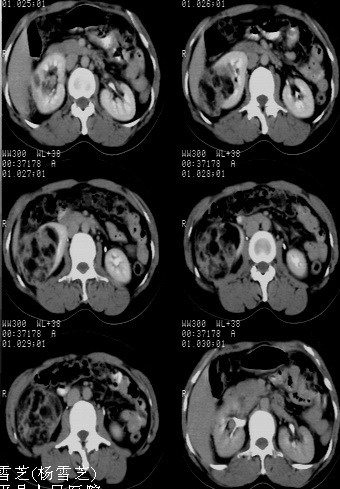

标题: CT24780:女 41岁 右肾多发低密度占位性病灶 [打印本页]

标题: CT24780:女 41岁 右肾多发低密度

女 41岁 超声检查:右肾多发实质性包块,性质待查(提示:错构瘤或其它病变),临床病史不详。